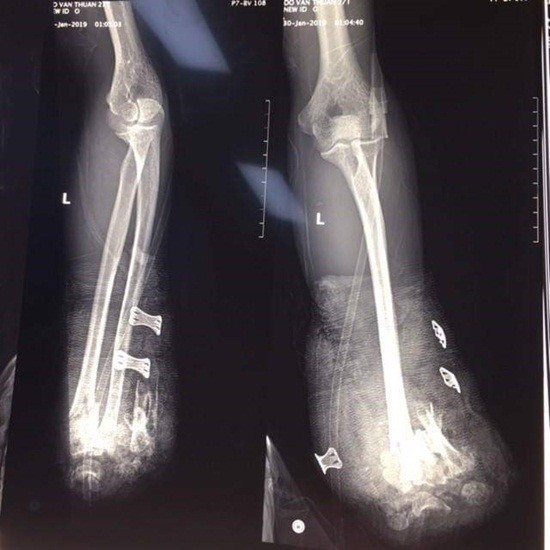

Hình ảnh chụp X-Quang 2 bàn tay bị cụt do pháo nổ. Ảnh: Báo Công lý

Bệnh nhân đã được mổ cấp cứu cắt cụt để ngỏ 1/3 giữa cẳng tay phải, cắt lọc cơ dập nát cẳng tay trái, kết xương hàm dưới. Sau mổ, bệnh nhân phải điều trị tiếp tại khoa Hồi sức tích cực của bệnh viện, theo báo Công an TP.HCM đưa tin.